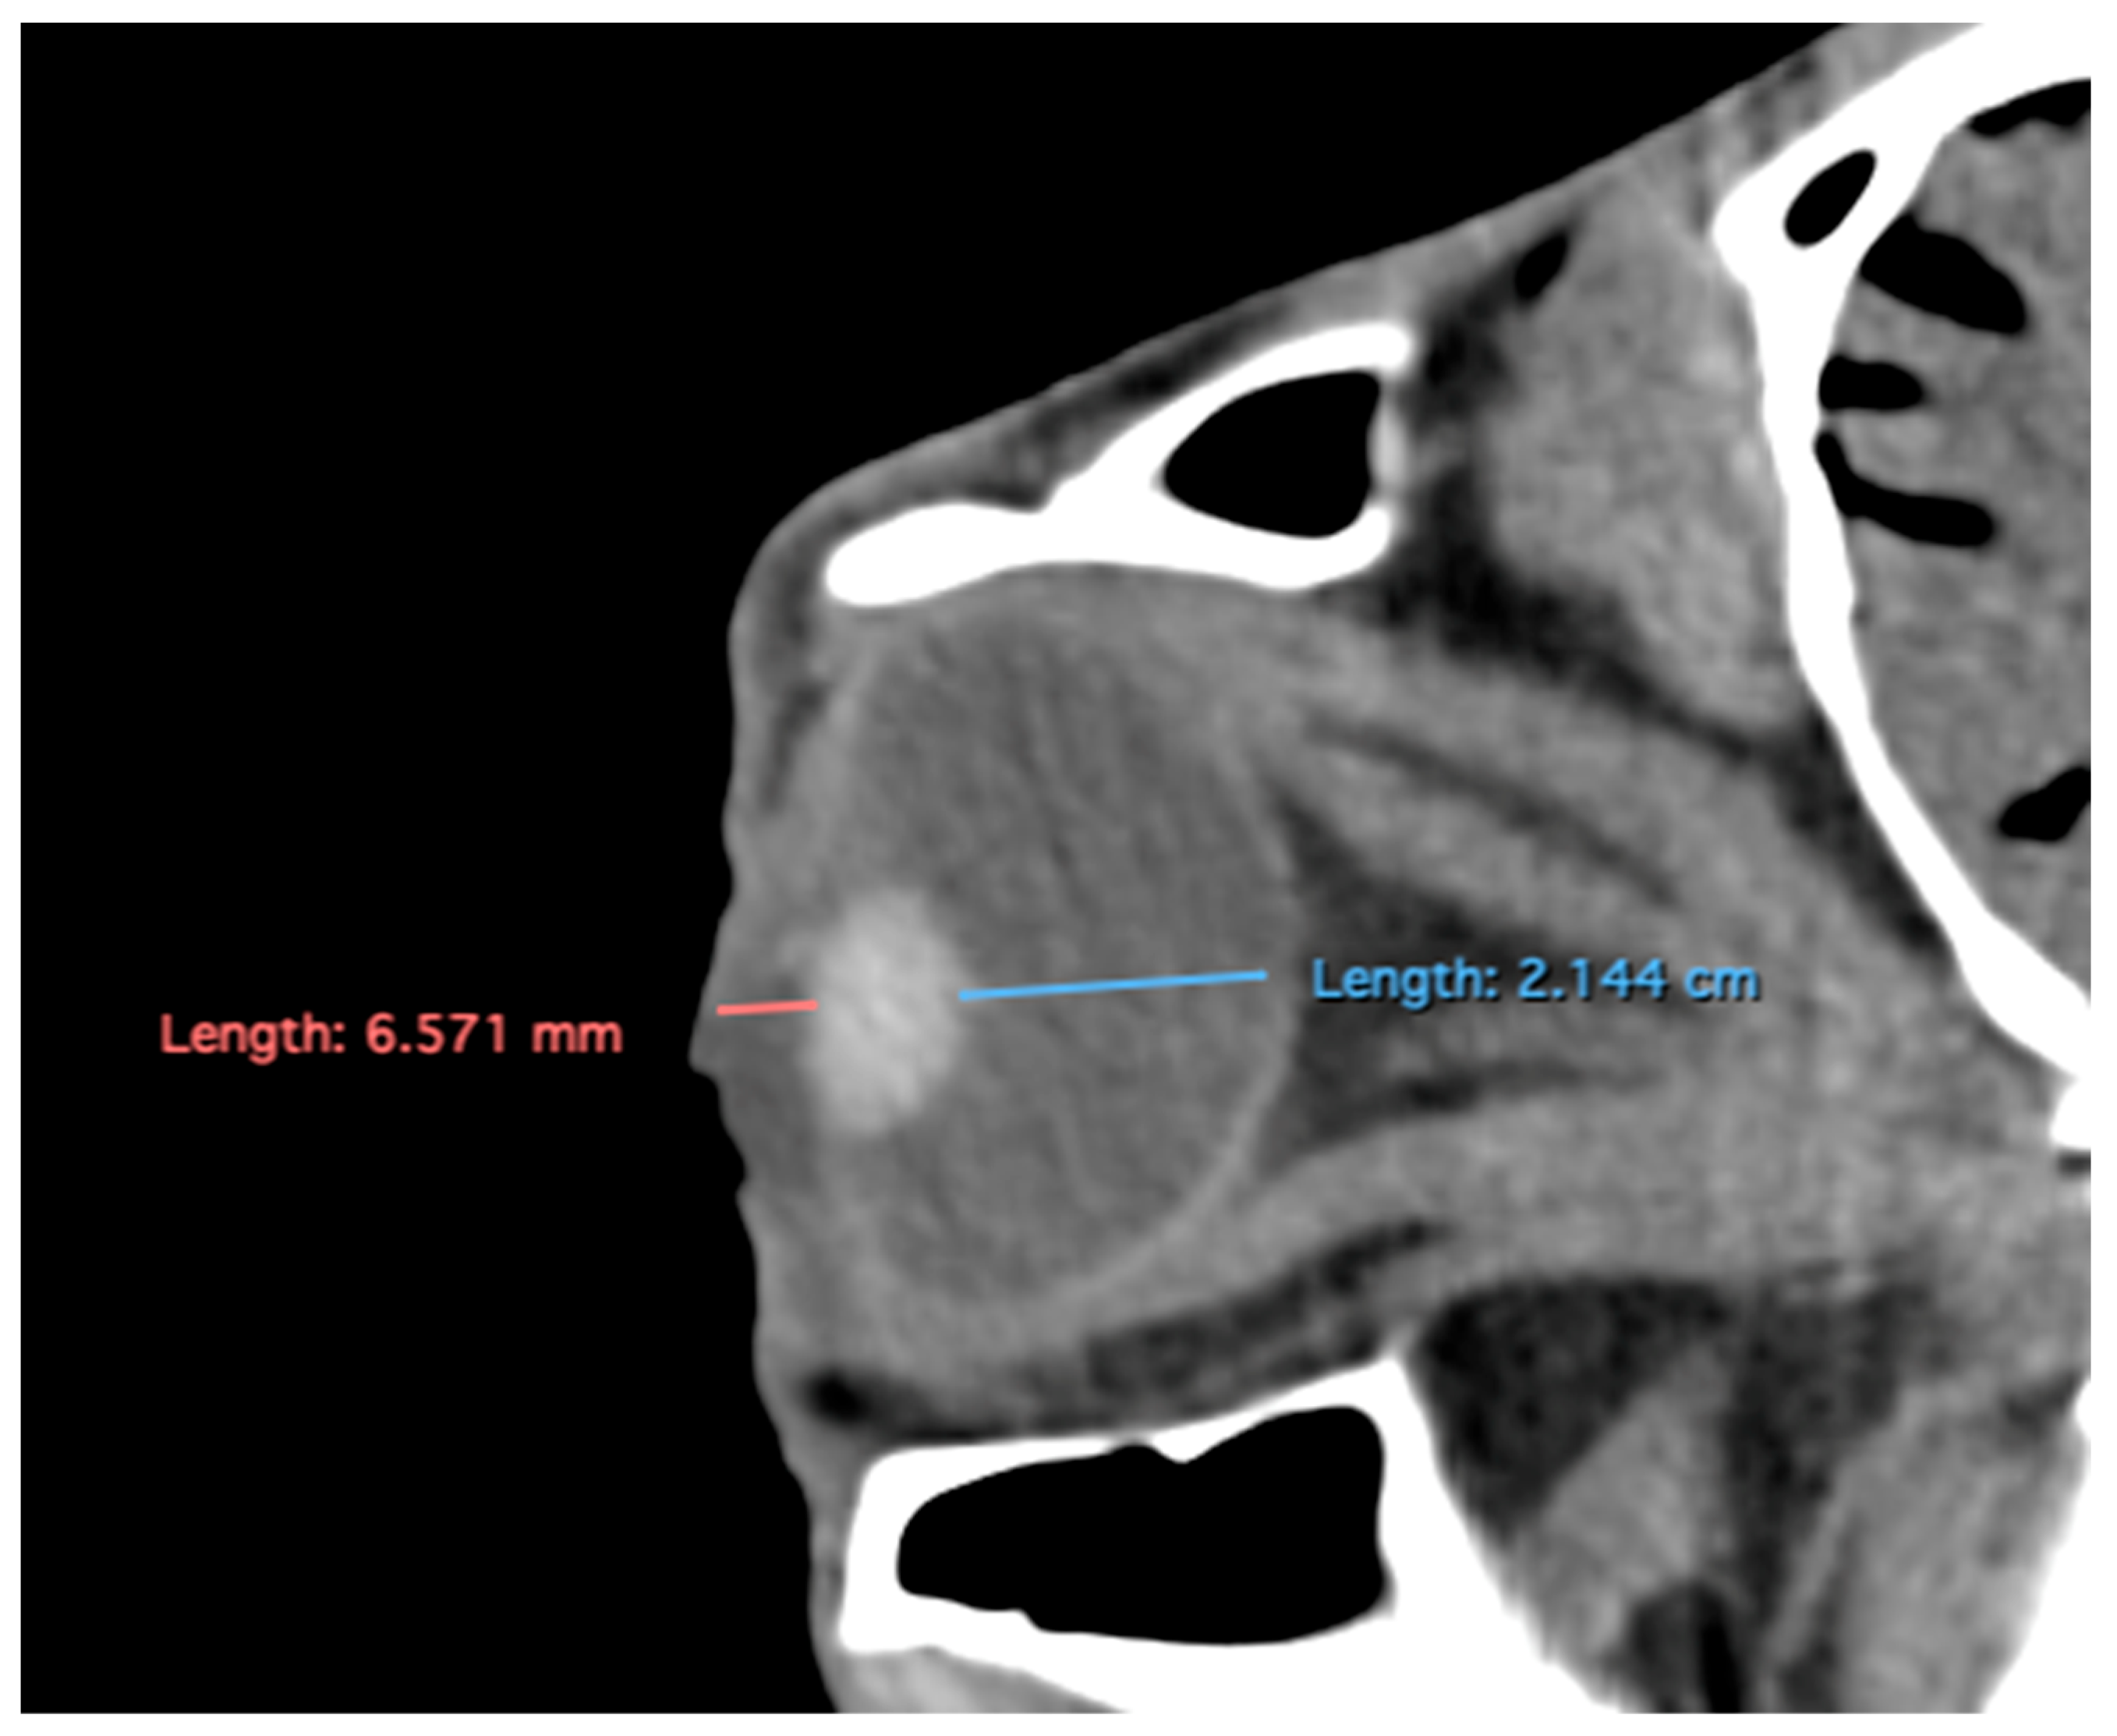

- Anterior and posterior chambers width: Maximal lateromedial distance across the anterior and posterior chambers (Figure 5).

Figure 5.

Transverse multiplanar reconstruction (MPR) image showing the widths of the anterior and posterior chambers, represented by the maximal latero-medial distance across each chamber.